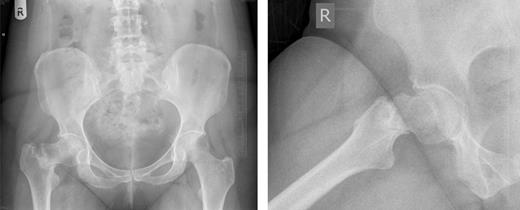

Pelvic and right hip radiograph's taken 5 months after the onset of symptoms demonstrating the fracture neck of femur.

During this 5-month period the fracture displaced, with shortening of the femur and varus deformity of the hip. Clinically, this resulted in a leg-length discrepancy of 4 cm and significant abductor weakness with the positive Trendelenburg test. The patient required a walking stick for mobilization and struggled to continue working. These clinical findings were easily elicited from orthopaedic examination and should have alerted the clinician to the diagnosis.